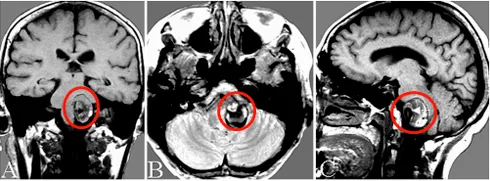

图1A-C:术前磁共振扫描显示部分血栓形成的VA-PICA动脉瘤,并压迫脑干。

图1D:术前左侧VA造影显示大量血栓形成的VA-PICA动脉瘤的灌注部分(箭头);图1E:术前左侧VA血管造影,VA-PICA动脉瘤合并巨大血栓形成,显示动脉瘤灌注部分(星形)和不同直径的左侧VA(箭头)和PICA(双箭头);图1F:磁共振血管造影显示VA-PICA动脉瘤部分血栓形成(箭头)。